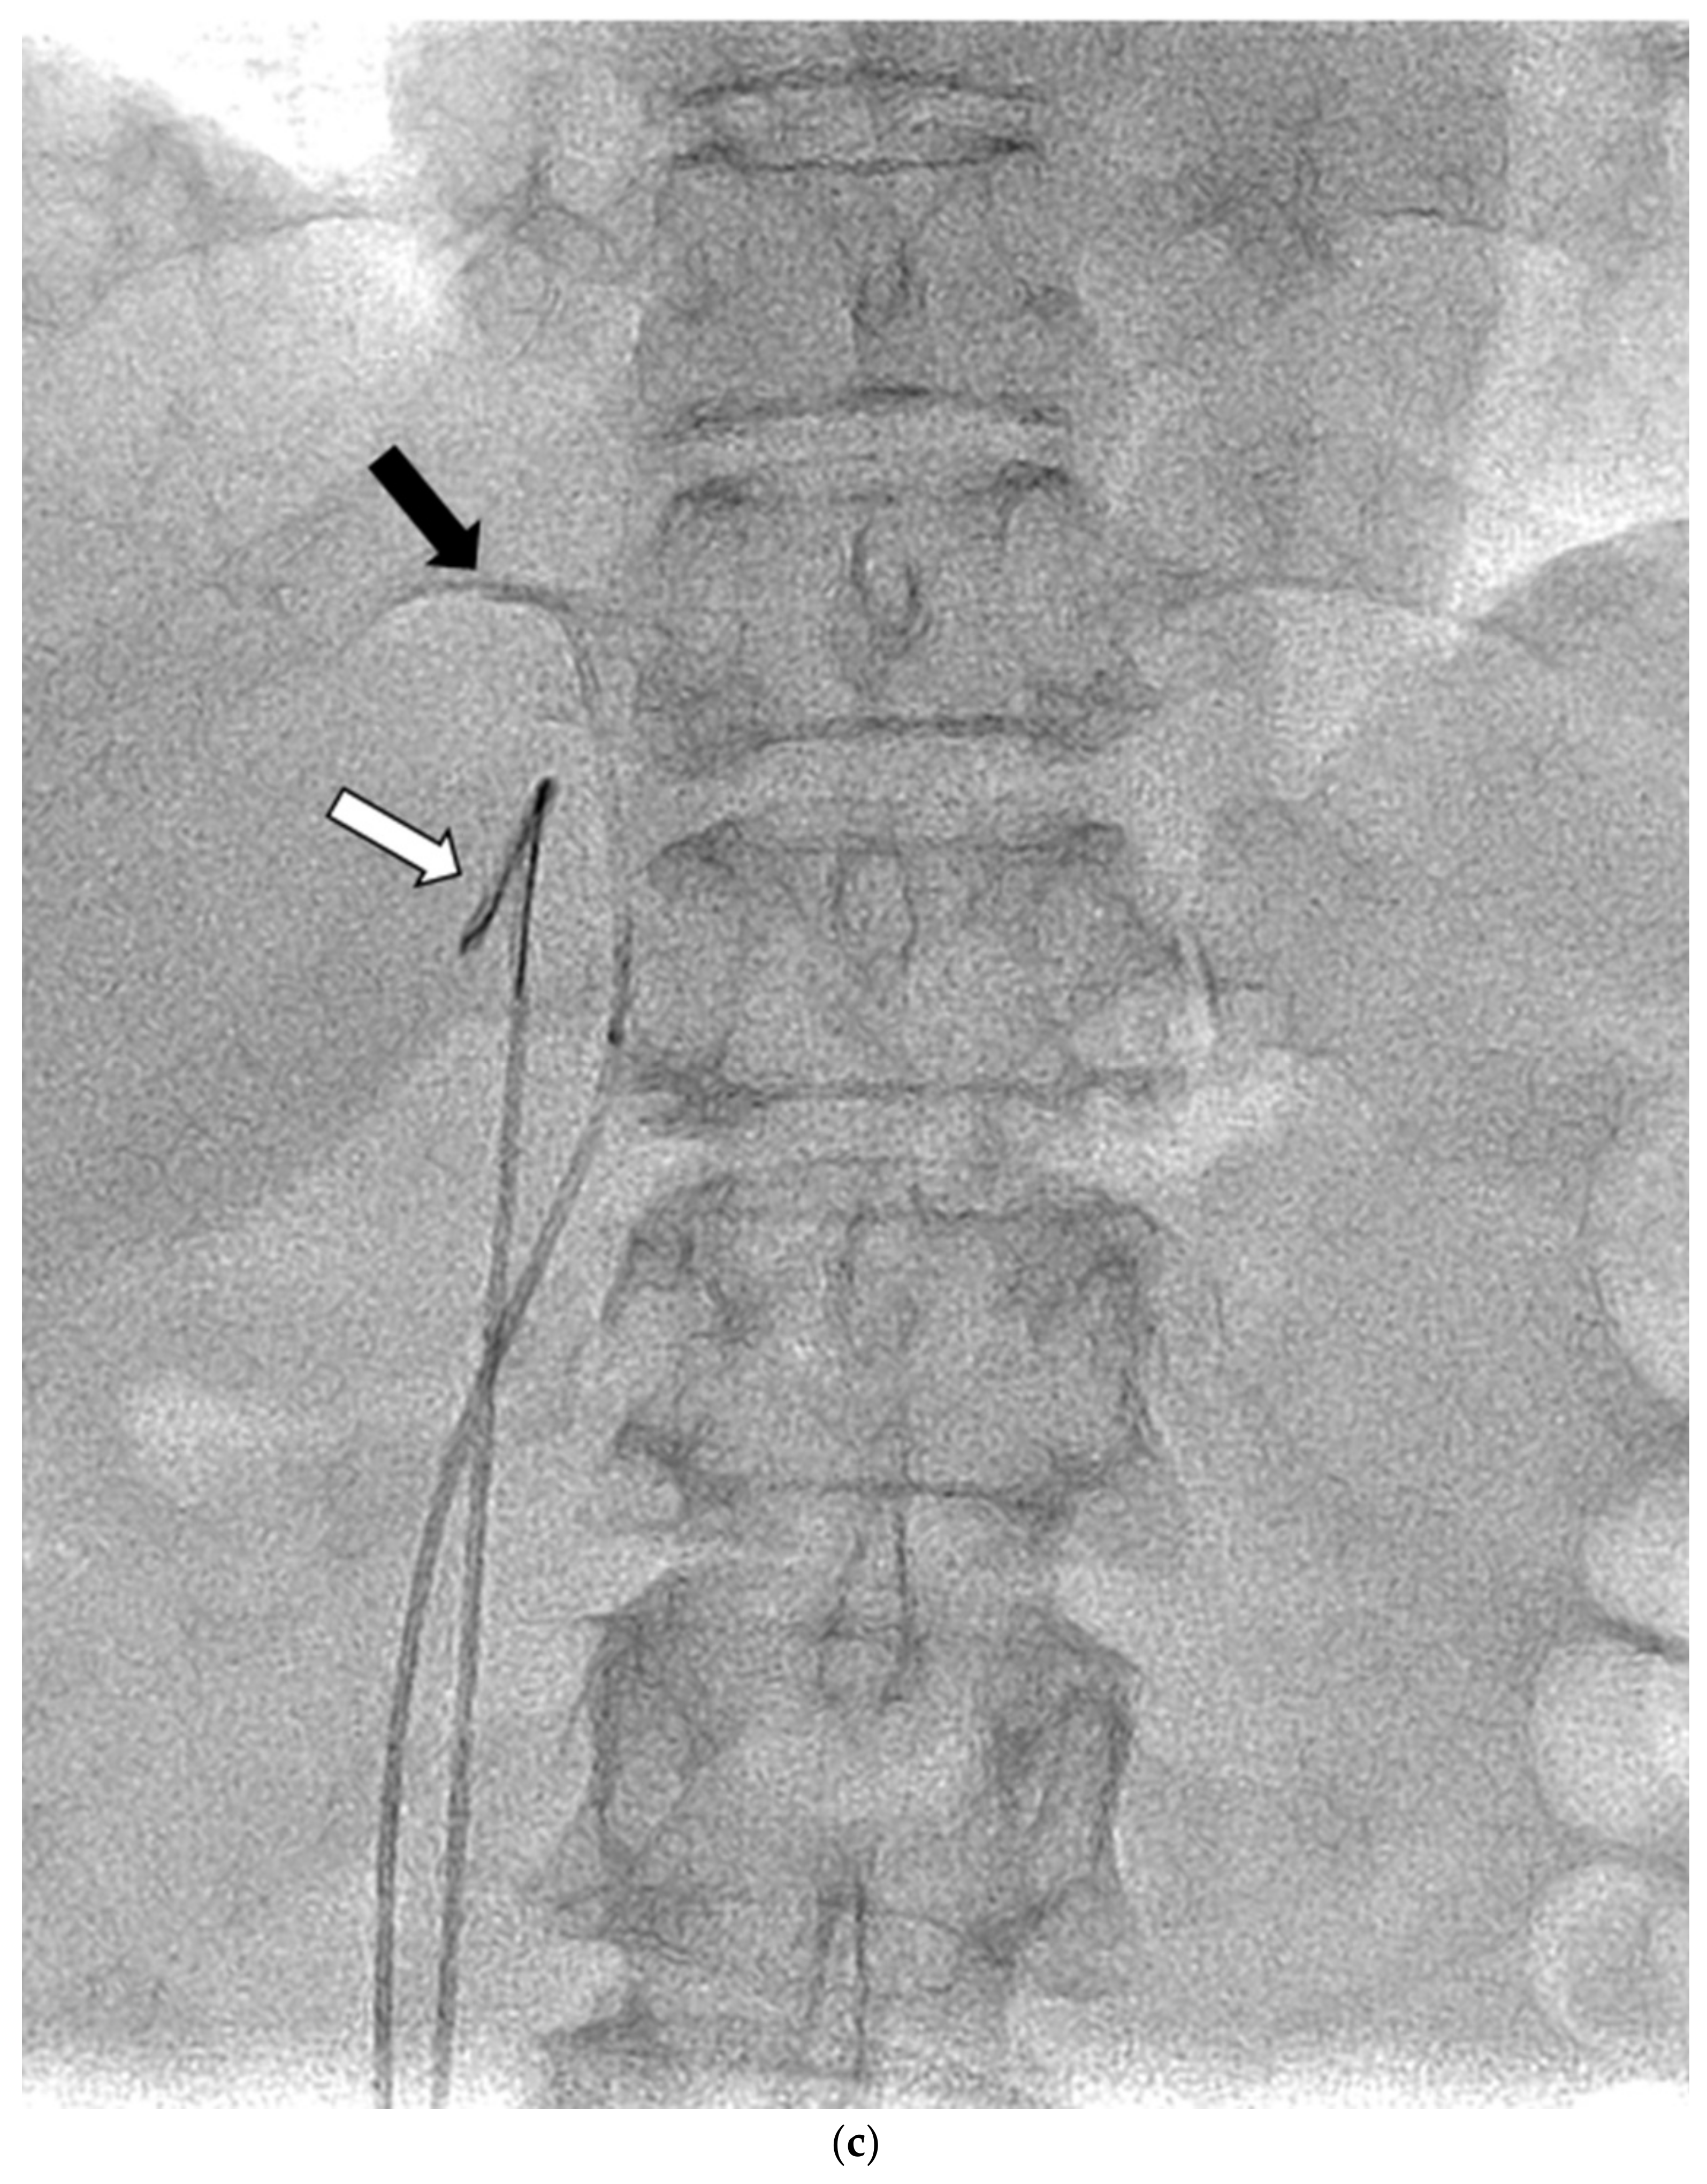

AVS was always conducted by 2 or 3 senior radiology residents or a radiologist with supervision by one of four interventional radiologists, after the administration of anticoagulant therapy with 3000 units of heparin. Under local anesthesia, 4-Fr sheaths were percutaneously inserted in the femoral veins of both legs. Before and after (between 15 and 30 min) bolus injection of 0.20 mg of the adrenocorticotropic hormone (ACTH) (cosyntropin), at least 3 mL of venous blood were sampled from the following four sites: the lowest point of the inferior vena cava (IVC) and the left AdV, the right AdV, and the IVC at one vertebral level above its confluence with the right AdV (the substitute right AdV [S-rt. AdV]). For the S-rt. AdV, the tip of the catheter was positioned on the same side of the IVC as the right AdV. Figure 1 shows how the positions of the S-rt. AdV were determined. For cannulation of the left AdV, a 4-Fr catheter of Simons-type (Terumo, Tokyo, Japan) and a 1.7-Fr microcatheter (Boston Scientific, Marlborough, MA, USA) were mainly used, and sampling from the main trunk of the left AdV was conducted via a 4-Fr sheath (Medikit, Tokyo, Japan) inserted into the left femoral vein. For cannulation of the right AdV, a 4-Fr Cobra-type (Medikit, Tokyo, Japan) or Hook-type (Medikit, Tokyo, Japan) catheter inserted into the right femoral vein via a 4-Fr sheath was used. The same microcatheter was used for the right AdV if blood could not be withdrawn from the 4-Fr catheter. Digital subtraction angiography (DSA) was performed using an Allura Xper FD20 (Philips Healthcare, Best, Netherland) and a Infinix 8000v (Canon Medical Systems, Tochigi, Japan). For patients in whom it was difficult to determine whether the catheter had entered the right AdV, an unenhanced or enhanced cone-beam CT was performed to confirm the locations of the catheters in the right AdV.

Figure 1.

Schematic diagram (a) and digital angiography (b,c) of the location of catheter placement in the S-rt. AdV. The catheter tip is placed at one vertebral level above the confluence of the IVC with the right AdV, and its orientation is adjusted so that it is pointing toward the right dorsal side in the same way as the right AdV.